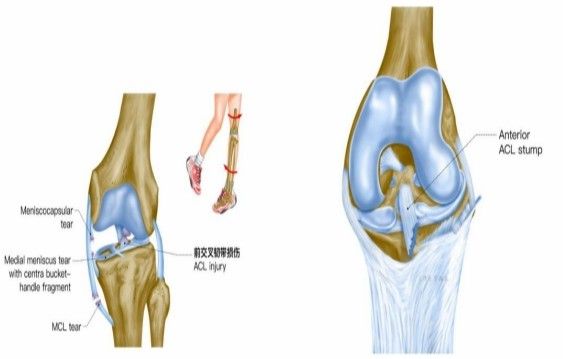

前交叉韌帶損傷

Anterior cruciate ligament injuryACL

致傷機制

單純前交叉韌帶損傷可發(fā)生于非負重條件下膝強力過伸時(如用力踢時未遇到抵抗),或小腿固定、暴力使股骨向后時。單純前交叉韌帶損傷少見,多合并脛側副韌帶、半月板的損傷,此三結構的復合傷在膝部韌帶損傷中最為常見(占52%)。損傷多發(fā)生于韌帶中部(占 72%),少數(shù)發(fā)生于股骨附著點撕脫骨折 (18%)或脛骨附著點撕脫骨折(4%)。損傷后關節(jié)內(nèi)出血、疼痛、活動受限、前抽屜試驗陽性。